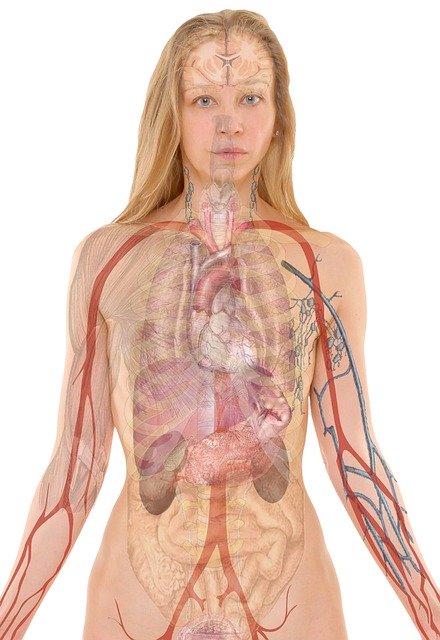

Anatomía macroscópica

A diferencia de la anatomía microscópica que requiere la utilización de instrumental para poder ver las partes estudiadas, la anatomía macroscópica se encarga del estudio de los órganos y sistemas de órganos de los seres vivos.

Anatomía humana

Es la ciencia que estudia las estructuras macroscópicas del cuerpo humano. Estudia las estructuras del cuerpo humano por sistemas, como son, el sistema esquelético, el nervioso, el vascular, etc.